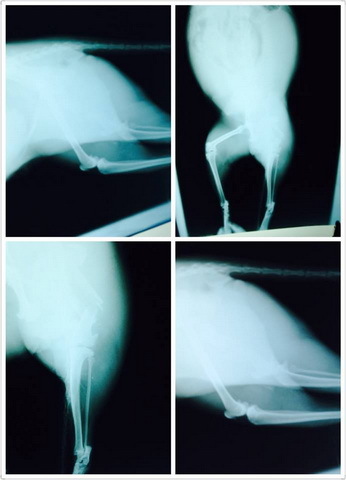

只好儘快去救援貓咪,大雨無情,在我們救援困難時又突下豪大雨,有目測到貓咪的腿已斷,肚子很腫有血水流出,貓咪躺在下大雨的泥濘中,但架設誘捕籠並沒有很順利的入籠,看到我們靠近又想跑,因雨太大,隔日6/8日中午我又再度前往救援,還好貓咪還在沒有離開,眼看她已經虛到不行,又不入籠的節骨眼上,只好冒險用網子撈她,還好貓咪沒有太激烈的反抗,順利救援到她,緊急送往台北市的長沁動物醫院,醫生照X光檢查了一下,左後腿骨折斷成三節,應該有開放性骨折,曾經岔出肉外,所以整條腿腫脹得很嚴重,但無法判斷傷了多久、有無感染,還有,貓咪帶著身孕。熱心的院長明天雖然休假,卻依然願意犧牲假期幫貓開刀,預計等開完後,就可以約略知道後續會遇到什麼樣的問題。

車禍造成的骨折讓亮亮不良於行

還讓她失去了肚子裡的寶寶

再來就是修養一個月後回診照x光看骨頭癒合與否

長的完整才可取出